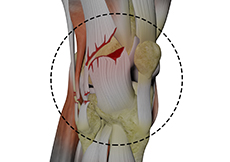

Anterior Cruciate Ligament (ACL) Tear

The anterior cruciate ligament, or ACL, is one of the major ligaments of the knee that is in the middle of the knee and runs from the femur (thighbone) to the tibia (shinbone). It prevents the tibia from sliding out in front of the femur. Together with posterior cruciate ligament (PCL) it provides rotational stability to the knee.

ACL Reconstruction

The anterior cruciate ligament is one of the major stabilizing ligaments in the knee. It is a strong rope like structure located in the centre of the knee running from the femur to the tibia.